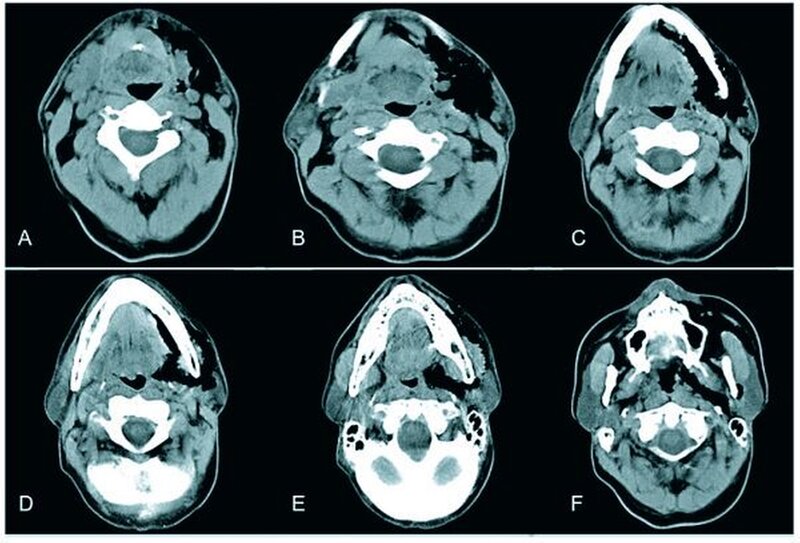

Zur gesicherten Diagnose von Lufteinschlüssen sind neben der klinischen Untersuchung Thoraxröntgenaufnahmen in zwei Ebenen anzufertigen. Die unteren Halsweichteile als auch das Mediastinum sind hier zur Beurteilung ausreichend abgebildet [Terzic et al., 2006]. Zur genaueren Darstellung der Ausdehnung von Emphysemen ist eine Computertomografie des Kopf-Hals-Thorax-Bereiches empfehlenswert [Lopez-Pelaez et al., 2001].

Dentalanamnestisch berichtete der Patient, dass die konservierenden und prothetischen Restaurationen vor etwa fünf Jahren erneuert wurden. Vor über 25 Jahren wurde Zahn 36 endodontisch behandelt und nachfolgend eine Wurzelspitzenresektion mit retrograder Amalgamfüllung durchgeführt. Halbjährlich stellte sich der Patient zur zahnärztlichen Kontrolle vor und ließ regelmäßig sein Gebiss professionell reinigen. In der ersten klinischen Untersuchung zeigte sich eine teigige, leicht erythematöse Schwellung der linken unteren Gesichtshälfte. Die Haut war weich und eindrückbar. Teilweise ließen sich Krepitationen auslösen. Die maximale Mundöffnung war mit 26 mm deutlich gemindert. Intraoral zeigte sich eine dezente Rötung der Gingiva im Bereich der mesiobukkalen Wurzel des Zahnes 36. Die übrigen Schleimhäute inklusive Oropharynx und Tonsillenregion waren reizlos. Bei der Beurteilung des Zahnfleisches fiel an Zahn 36 im Bereich der mesiobukkalen Wurzel eine vestibuläre Rezession von drei Millimetern auf. Die resezierte mesiobukkale Wurzel war bis apikal sondierbar.